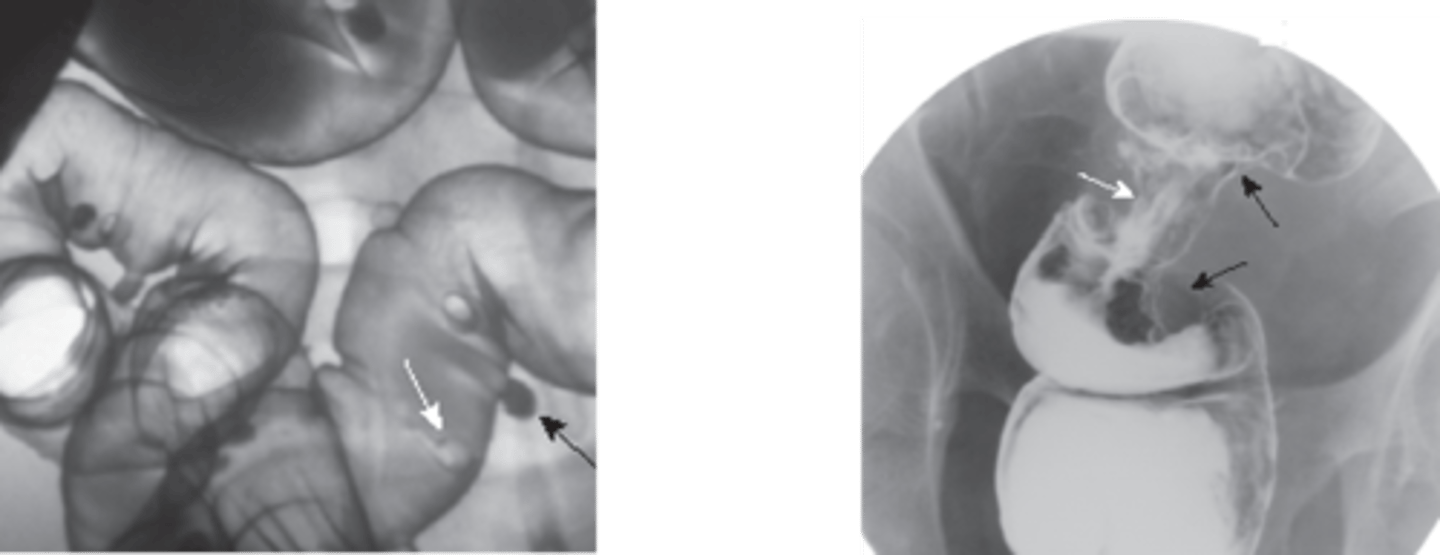

apple core lesion- colon CA

diverticulosis